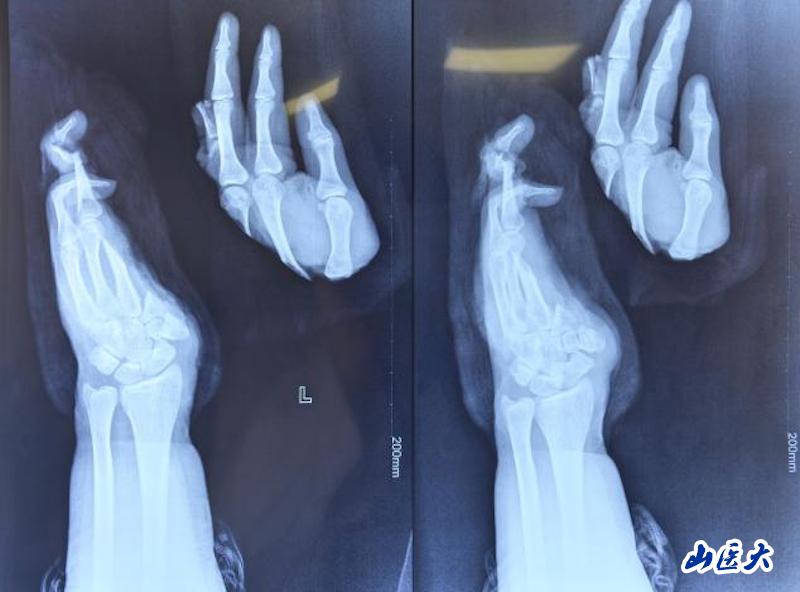

患者小张(化名)是一名在校大学生,为减轻家庭负担,利用课余时间勤工俭学。然而,一次机器操作不慎,导致他的左手掌完全离断。当患者抵达时,离断的手掌被一同送来。我校附属第二医院西院区迅速启动绿色通道,骨手显微组当日值班的李广荣、武永辉、房格三位医师第一时间赶到,患者左手掌中部完全离断,创面污染严重,血管、神经、肌腱等关键结构损伤复杂。医师们马上就位并立即准备再植手术。

手掌血管直径仅0.3-0.5毫米,不足普通针孔大小;医生需要在手术显微镜下,使用比头发丝更细的11-0缝线,将断裂的血管重新吻合。手掌包含27块骨骼、多条肌腱、复杂的神经血管网络;再植手术必须依次完成骨骼固定、伸屈肌腱修复、神经对接、动脉静脉吻合等多个环节,每个环节都要求极高的精度和恰当的顺序安排。